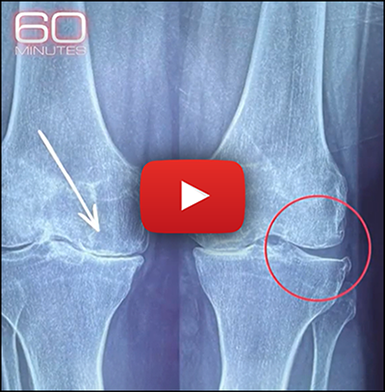

If your joints are bone one bone, knees grinding with every step due to "Old Uncle Arthur"…

Early clinical trials in 2026 have discovered a safe, natural at-home protocol that's reversing joint damage and restoring pain-free movement, even in severe cases. |